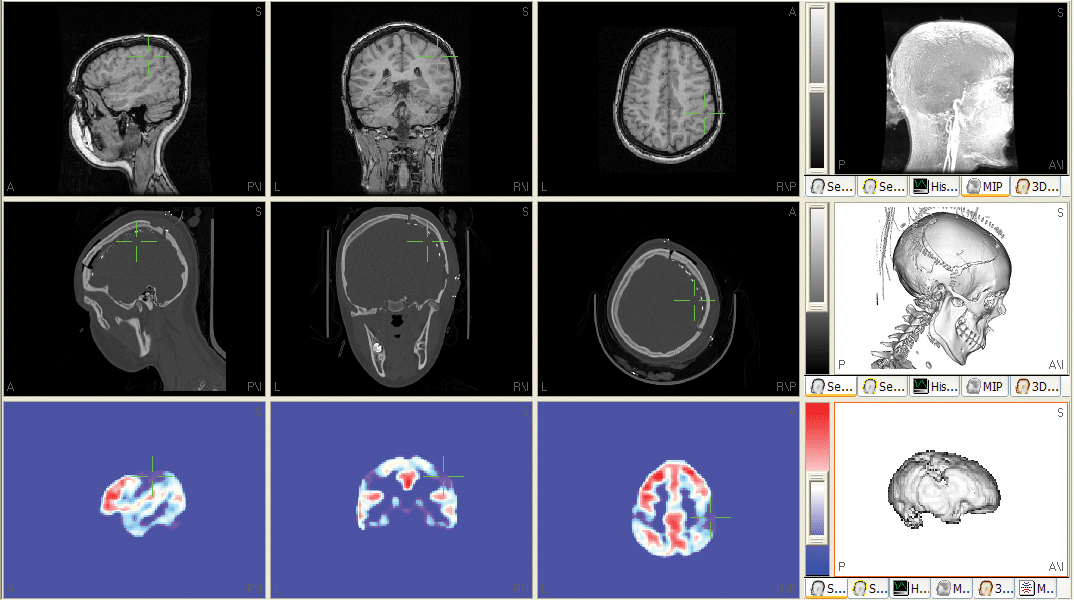

SWARM current density reconstructions (sLORETA-weighted minimum norm)

In contrast to sLORETA, SWARM results in currrent densities (similar to MNLS) instead of statistical measures for e.g. cortically constrained Current Density Reconstructions (CDRs).

Multimodal source reconstructions from combined EEG and MEG data

EEG and MEG data can be combined after a Signal-to-Noise-transformation for increased information content and improved spatial resolution of source reconstructions. A conductivity factor can be fitted to take care of the not very well known in vivo conductivities that affect the EEG, but not the MEG solutions.